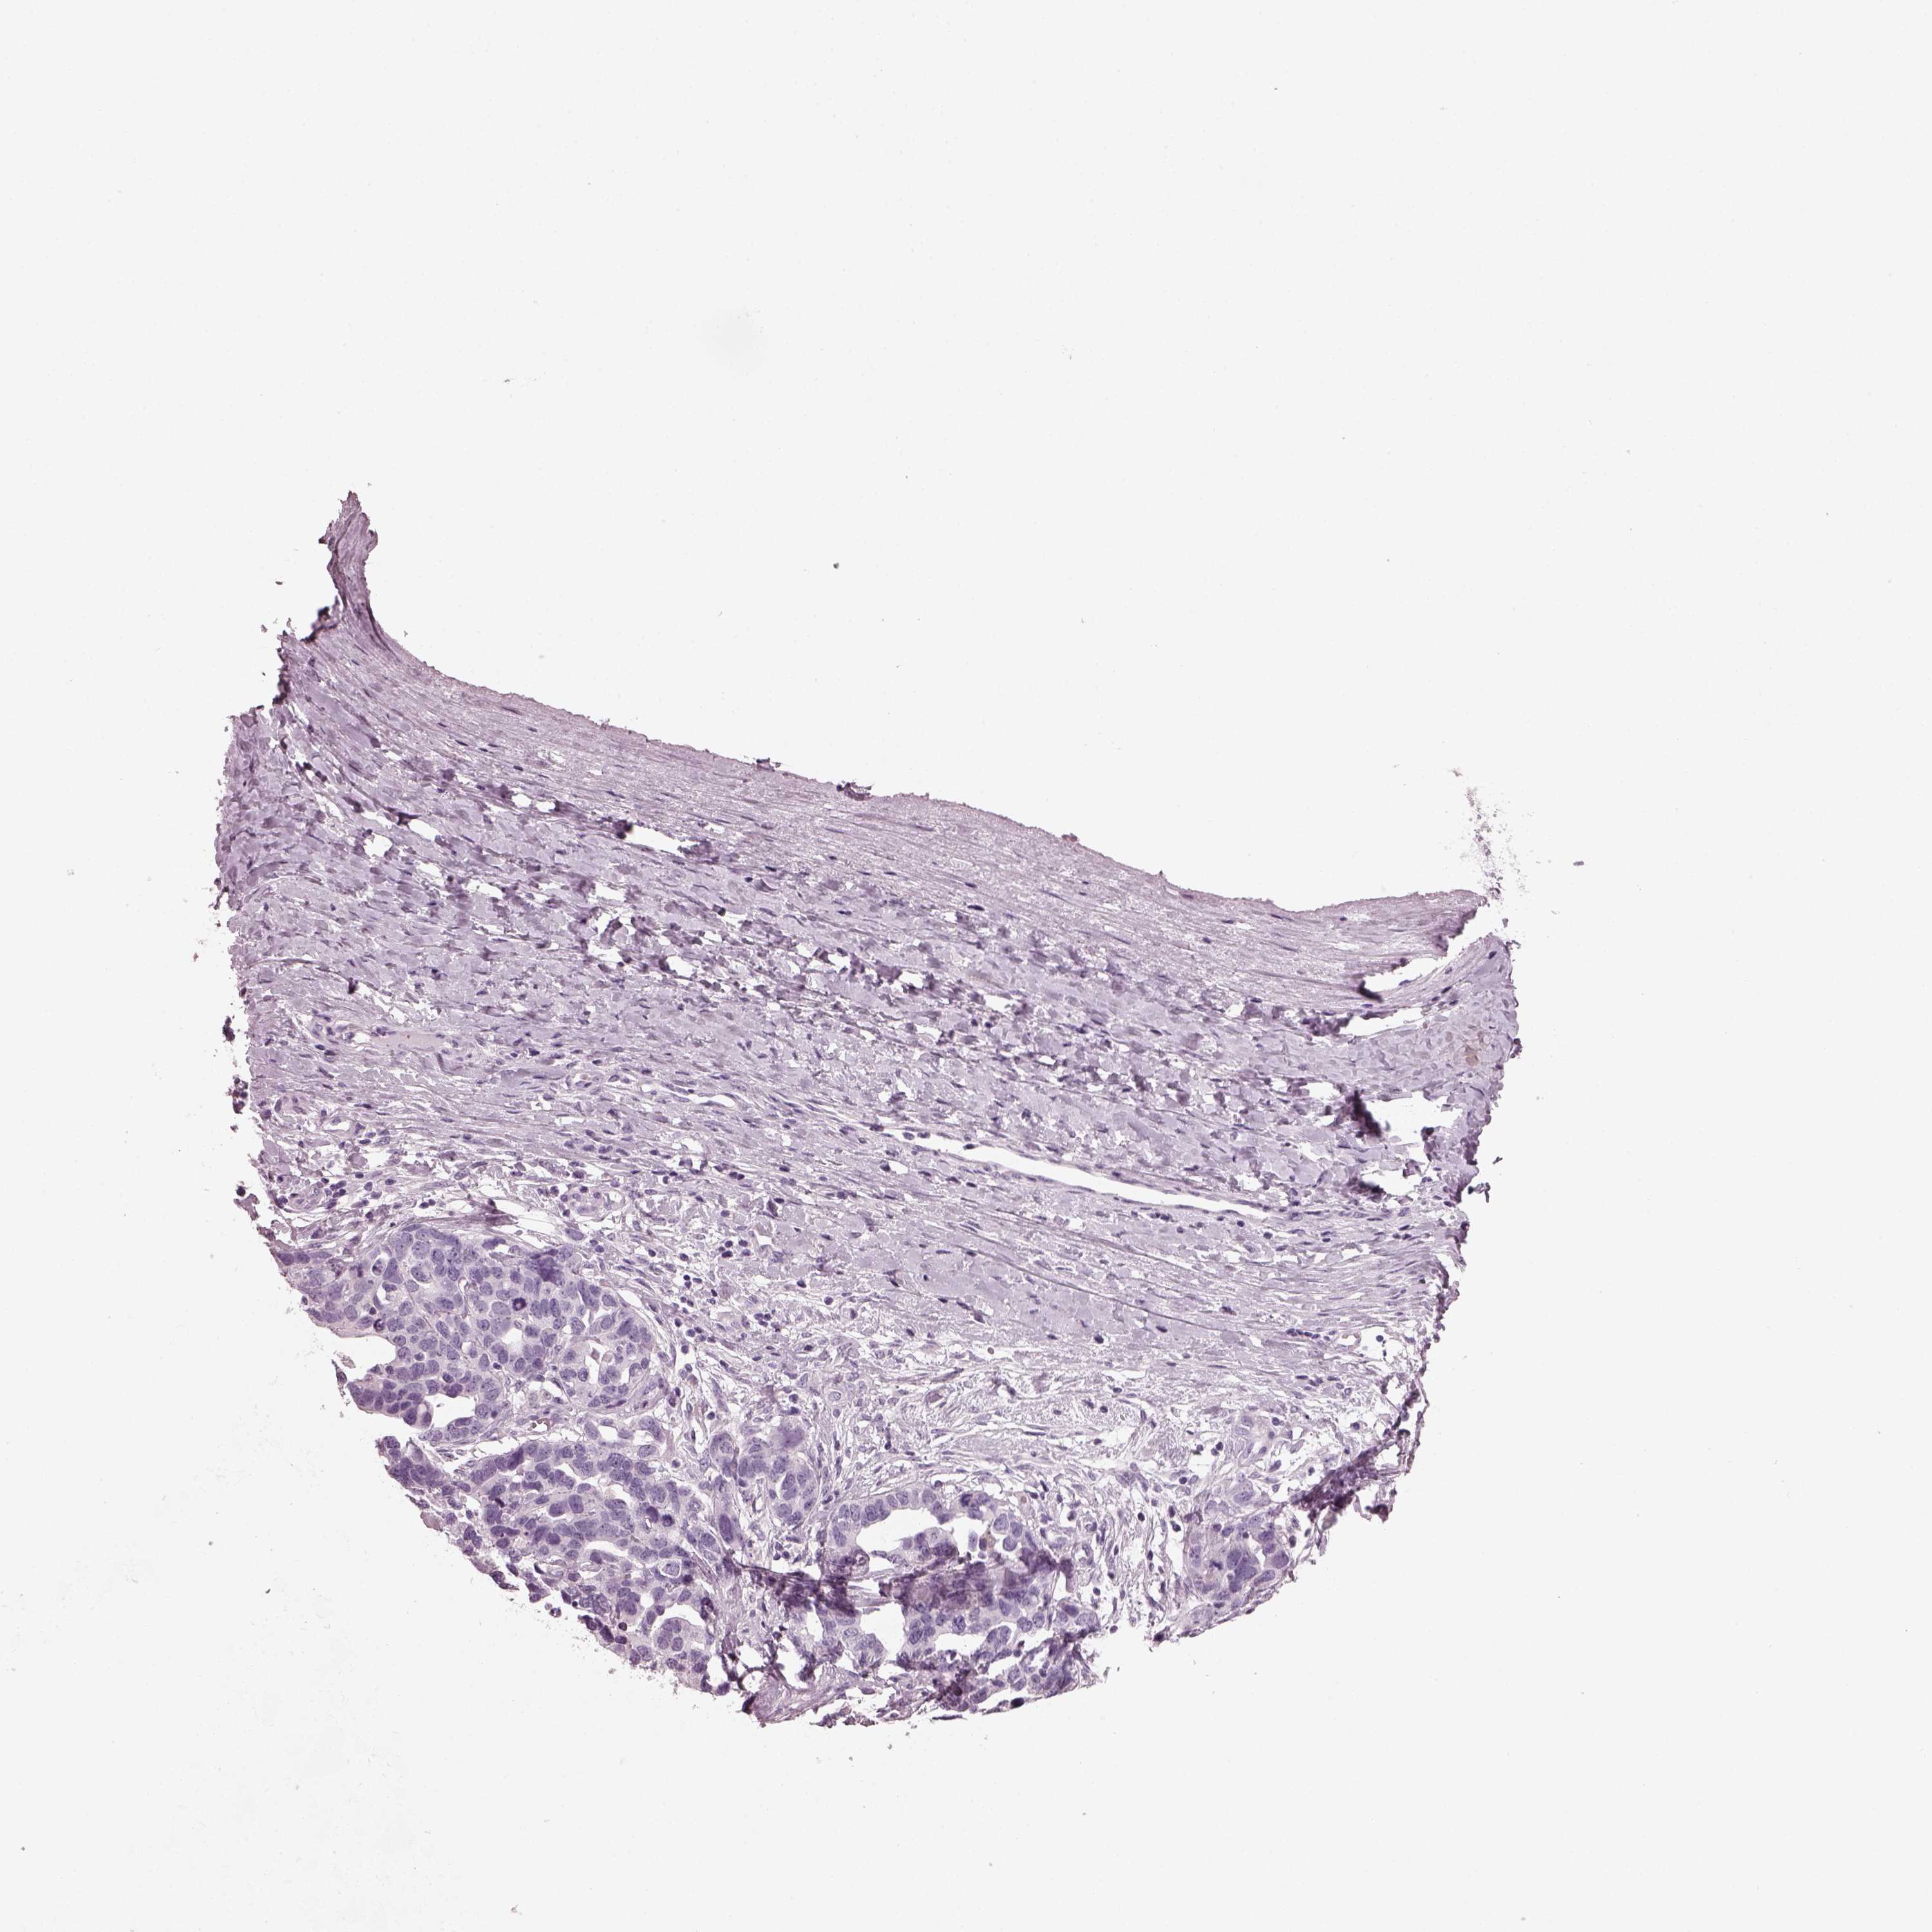

OVARIAN CANCER - Protein expressioni

A mouse-over function shows sample information and annotation data. Click on an image to view it in a full screen mode. Samples can be filtered based on level of antibody staining by selecting one or several of the following categories: high, medium, low and not detected. The assay and annotation is described here.

Note that samples used for immunohistochemistry by the Human Protein Atlas do not correspond to samples in the TCGA dataset.

Antibody stainingi

Antibody staining in the annotated cell types in the current human tissue is reported as not detected, low, medium, or high, based on conventional immunohistochemistry profiling in selected tissues. This score is based on the combination of the staining intensity and fraction of stained cells.

Each image is clickable and will lead to virtual microscopy that enables deeper exploration of all samples and also displays staining intensity scores, fraction scores and subcellular localization as well as patient and tissue information for each sample.

Antibody HPA015783

Antibody CAB022363

Cystadenocarcinoma, serous, NOS

Cystadenocarcinoma, mucinous, NOS

Carcinoma, endometroid